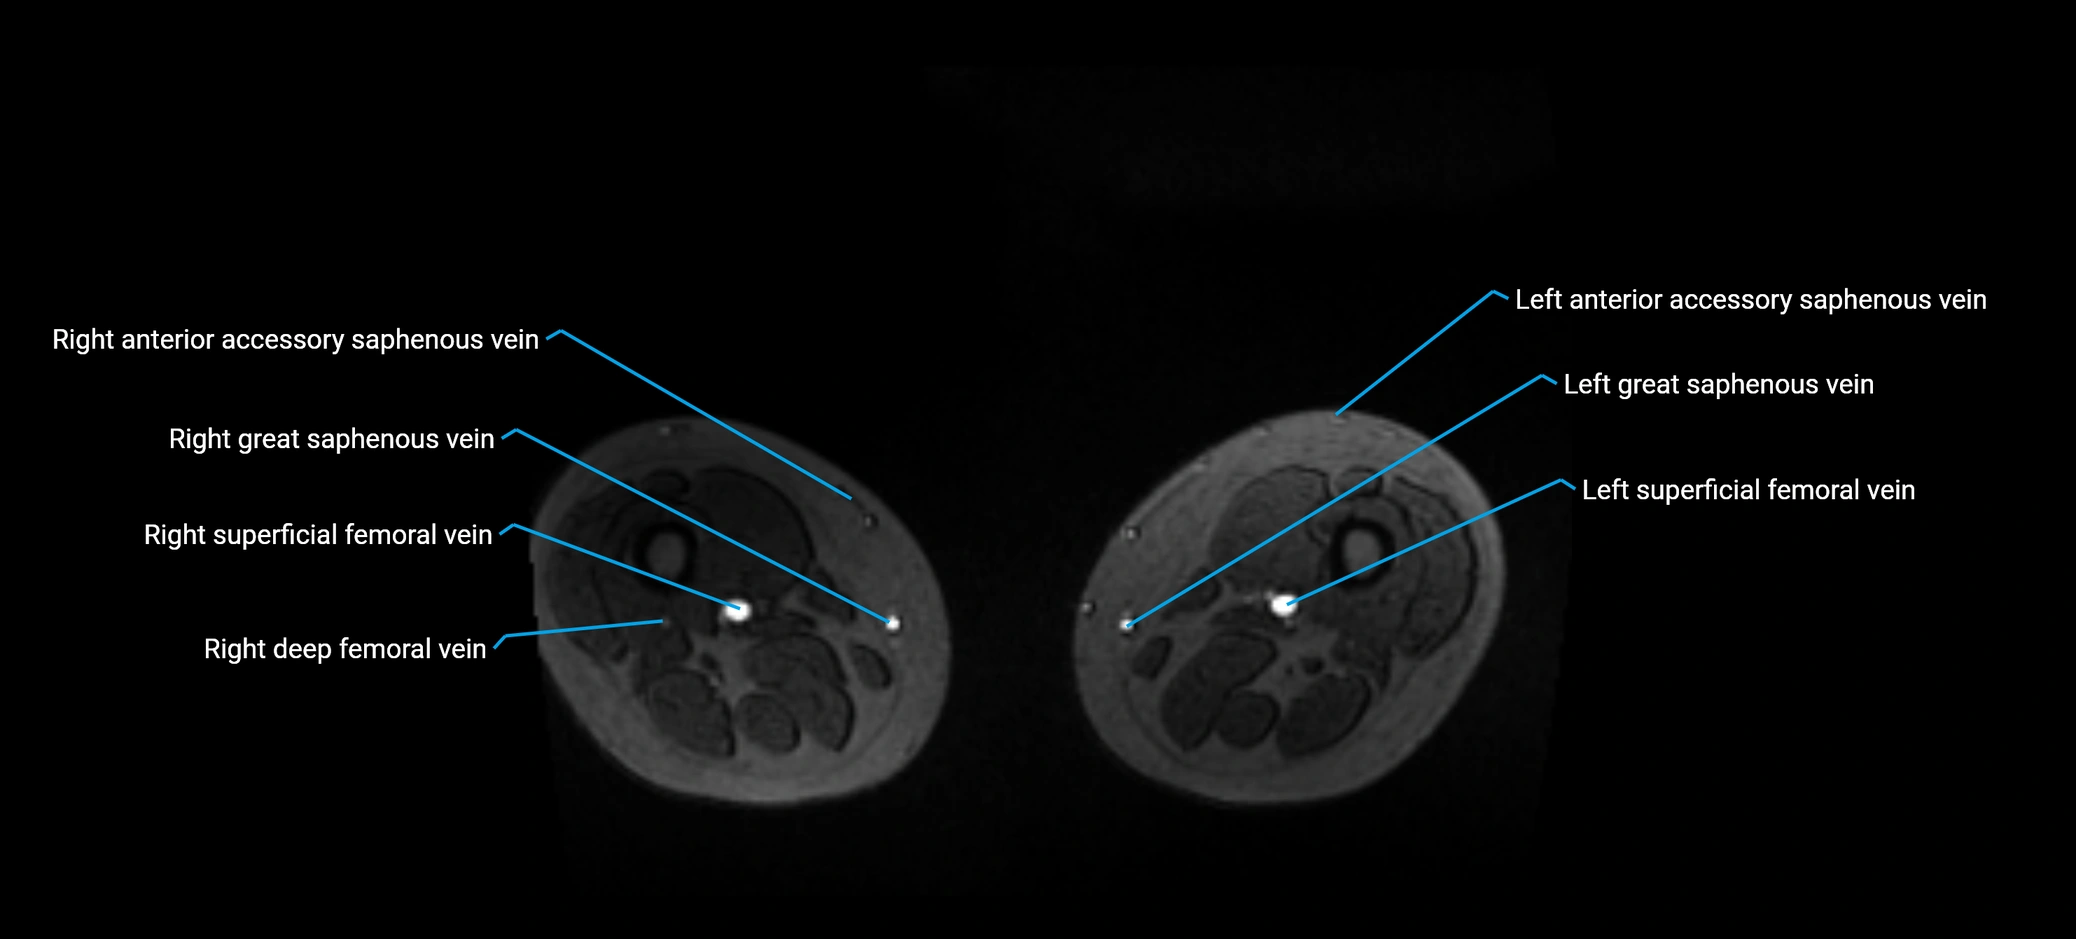

MRI image

image